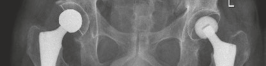

Radiographic Confirmation

Postoperative AP pelvis radiographs demonstrated bilateral uncemented THA with excellent component positioning. The acetabular shells were appropriately medialized with ideal inclination. The monobloc femoral stems were in neutral alignment, filling the metaphysis adequately without varus or valgus tilt. Leg lengths and global femoral offsets were symmetrically restored.

The lateral radiograph of the left hip confirmed appropriate anteversion of the acetabular component and central placement of the femoral stem within the medullary canal.

The lateral radiograph of the right hip similarly demonstrated excellent component alignment and seating of the uncemented monobloc stem.